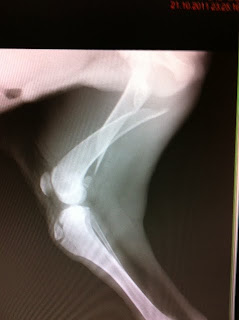

Pessoal, esse é o Tobby!

Uma amiga o encontrou em SP (cidade) e, como toda boa futura veterinária, pegou para cuidar!

Levou-o ao HV e, junto com outros amigos, financiaram sua cirurgia.

Ele estava atropelado, seu fêmur com fratura completa como mostra a radiografia.

Agora o Tobby está bem, se recuperando, porém, precisa de um lar!